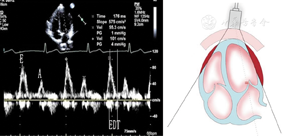

图11

标准心尖四腔切面引导脉冲波多普勒取样二尖瓣口舒张期跨瓣血流速度峰值E峰和A峰、A峰持续时间以及E峰减速时间测量方法